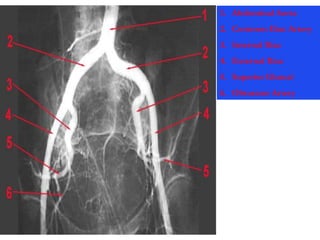

1. Abdominal Aorta

2. Common Iliac Artery

3. Internal Iliac

4. External Iliac

5. Superior Gluteal

6. Obturator Artery